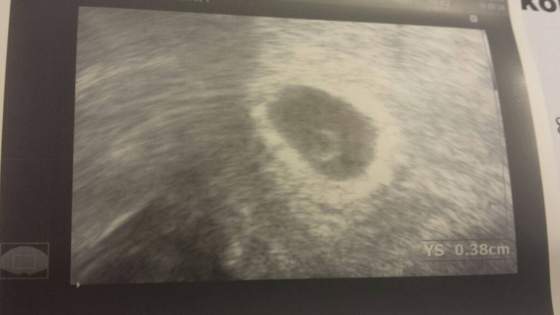

No dziwczyny ja tam z rana jak siknelam to nic nie widzialam a on mi fote przeslal na maila i nawet widac. Za 30 min bede w domu to postaram sie siasc na tablecie i spprobowac wam przeslac bo tak moja durna komora nie podola. A jak nie dzis to jutro z ranca dwa bo zasiade na kompie u rodzicow na dole. Ciekawe co jutro bedIe. Pretesta kupilam. Masakra ale jestem podjarana.... zeby tylko klopsa nie bylo